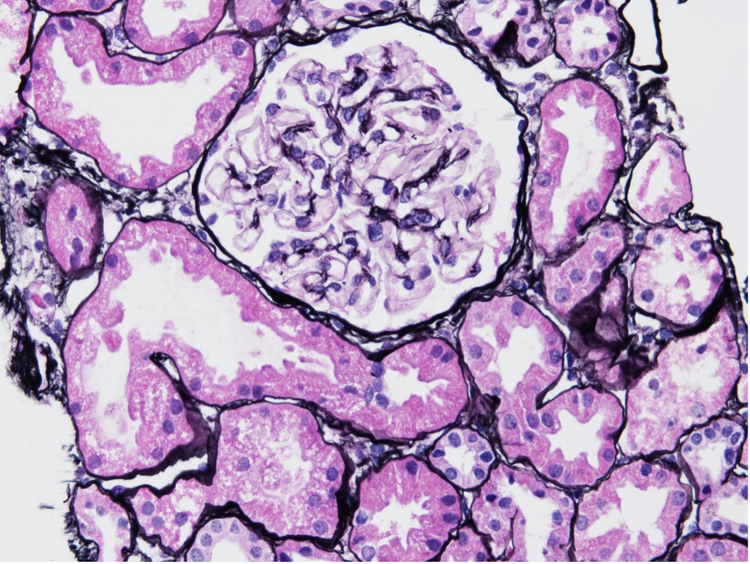

Por ejemplo, la Figura 1 expone muestras de riñón provenientes de pacientes en la fase temprana de NA - Clase 1, sin cambios glomerulares significativos en comparación con individuos sanos. 2

Figura 1. Muestra de biopsia renal con NA de Clase 1 y tinción de metenamina de plata de Jones.